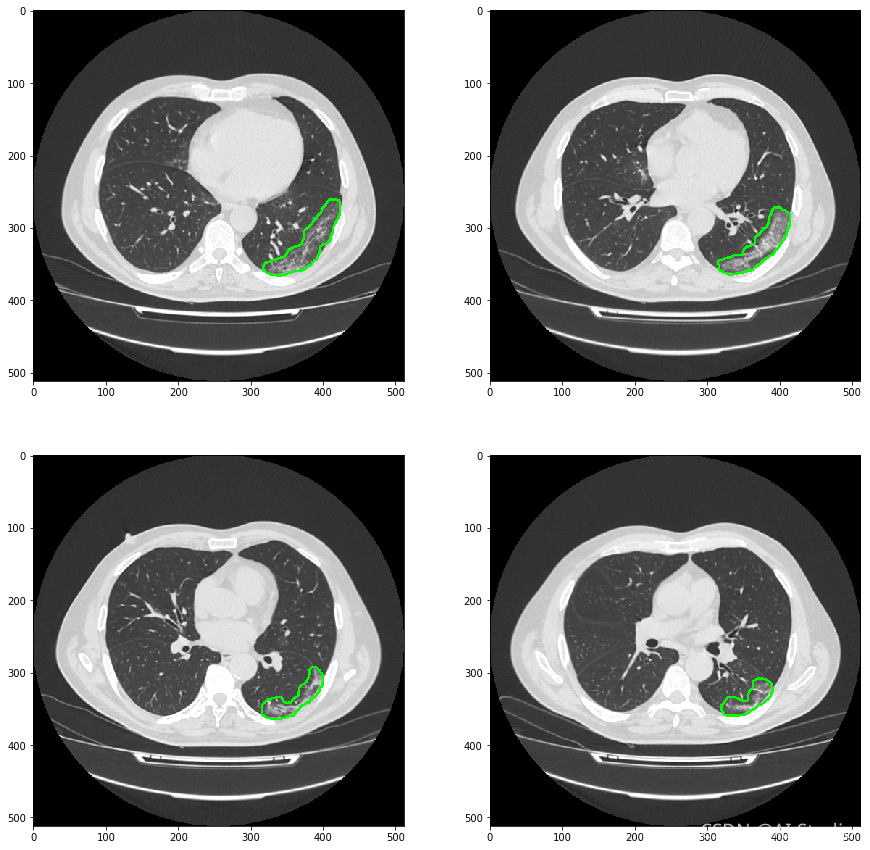

模型检测效果如下图:

对预测结果进行展示

可见模型对磨玻璃样病灶的细节分割并不是很好。但是这个项目的目地只是需要通过预测的mask结果在原图上画出病灶的轮廓,实现对病灶的检测和定位。告诉医疗那一层有磨玻璃样病灶,或者告诉医生那一层出现的磨玻璃样病灶面积是最大的。

对整个医疗数据图像文件Nifit文件进行推理

医学影像数据,一般是Nifit格式或者Dicom格式。是一种三维数据。因为训练过程中采用2D数据训练。最后对医疗影像数据进行推理时,需要一层层进行推理,并把最后结果再堆叠组合成三维数据。